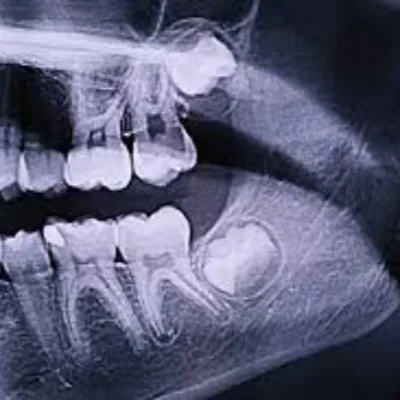

Wisdom Tooth Evaluation

Checking for impaction or alignment issues.